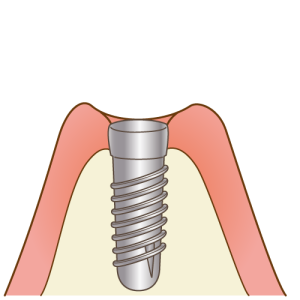

「インプラント」と呼ばれる人工歯根を歯を失ってしまった部分に埋め込み、その上に人工歯を装着することで、まるで自分の歯のような見た目や噛み心地を回復させることができます。

ブリッジや入れ歯と違い、周りの歯や組織に負荷をかけずに歯を作ることができるため非常に健康的で長持ちのする治療です。